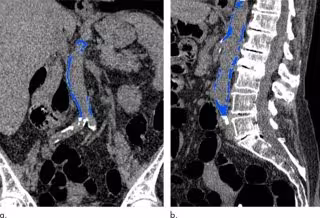

La TC se usa comúnmente para medir el calcio, un componente de la placa, en las arterias coronarias. También puede calcular el calcio en la aorta abdominal, el gran vaso que transporta sangre oxigenada a las extremidades inferiores. La aorta abdominal se puede ver en exámenes de imágenes abdominales como la colonografía por TC, también conocida como colonoscopia virtual, y en el estudio de diagnóstico para la colecistitis aguda, una inflamación de la vesícula biliar a menudo causada por cálculos biliares.

Para el nuevo estudio, realizado en la Escuela de Medicina y Salud Pública de la Universidad de Wisconsin en Madison, los científicos evaluaron la relación entre la calcificación aórtica abdominal en la TC y los eventos cardiovasculares en 829 pacientes asintomáticos con una edad media de aproximadamente 58 años.

UNA HERRAMIENTA DE DETECCIÓN

De los 829 pacientes, 156 (el 18,8 por ciento) tuvieron un evento cardiovascular importante. Los eventos ocurrieron casi siete años después de la TC, en promedio, e incluyeron un ataque cardiaco en 39 y muerte en 79. La calcificación aórtica abdominal basada en TC fue un fuerte predictor de eventos cardiovasculares futuros, superando el puntaje de riesgo de Framingham. La calcificación aórtica abdominal fue más de cinco veces mayor, en promedio, entre los que tuvieron un evento cardiovascular que entre los que no.

Los resultados apuntan al potencial de la evaluación de la calcificación aórtica abdominal como una herramienta de detección oportunista, algo que podría agregarse a otros exámenes sin la necesidad de tiempo adicional del paciente o dosis de radiación. Los pacientes podrían ser asignados a regímenes de tratamiento preventivo en función de sus categorías de riesgo cardiovascular.